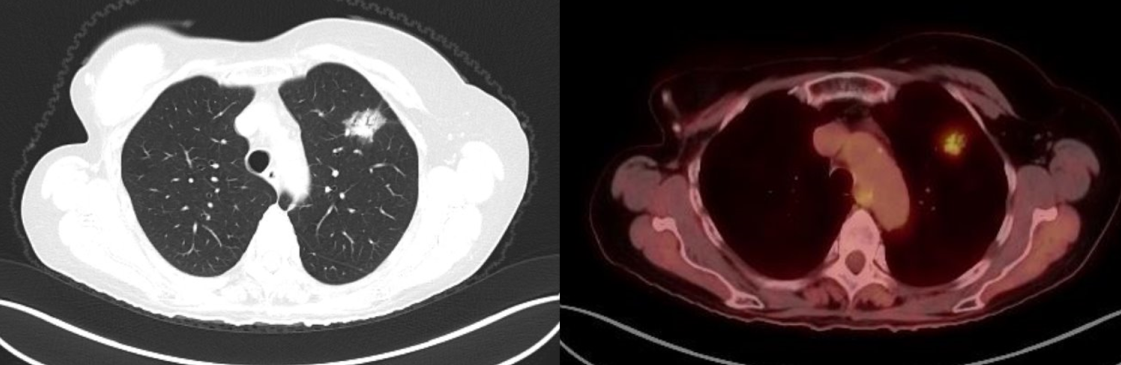

A 70-year-old woman with a past history of breast cancer in 2004 also had a nonperipheral pseudonodular ground glass appearance lesion in the left upper lobe since 2010, a core-needle biopsy in 2012 and 2015, and a diagnosis of benign pneumocytoma (Figure 1). Since 2018, the lesion had a growth of the solid component in chest computed tomography scan, so a positron emission tomography scan was performed, which showed an increased metabolic uptake in the lesion (SUV max 2.77) (Figure 2).

Figure 2

With the suspicion of malignant growth within the lesion (probable lepidic adenocarcinoma), a sublobar anatomical resection was indicated to avoid a left upper lobectomy.